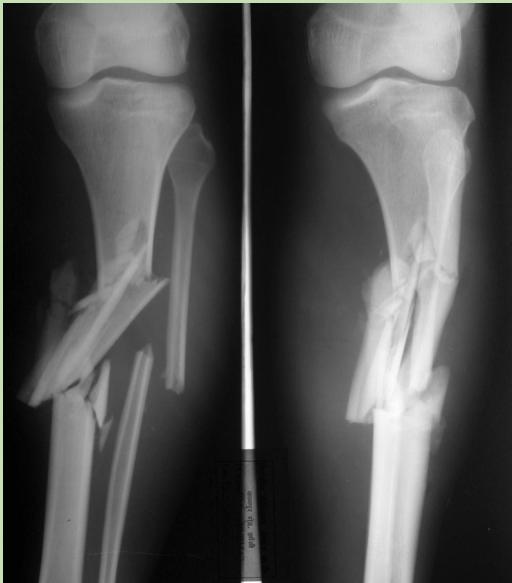

Case Scenario 1: Open Tibia Fracture

- A 30-year-old man was involved in a car accident

- Large wound at the anterior aspect of left leg with severe deformity and bone exposed